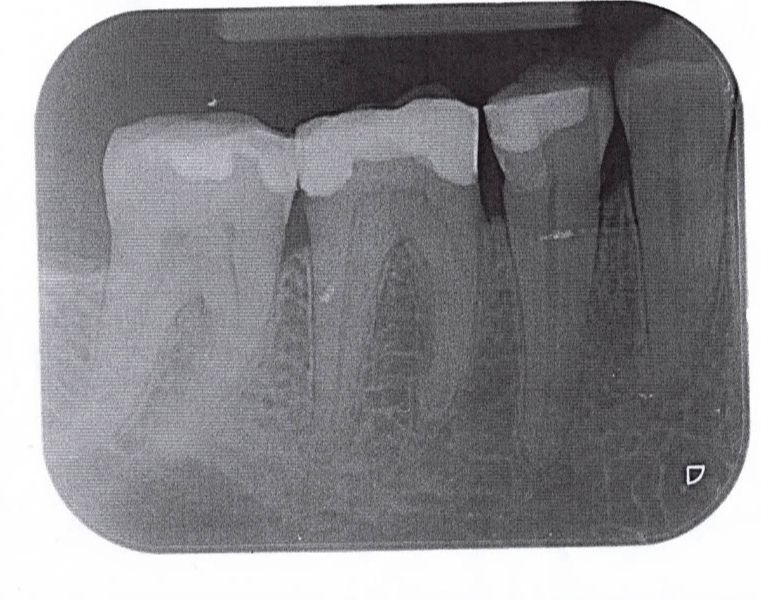

Teilkronen im Unterkiefer

Unterkiefer

46 PKM pw 36

45 PKM pw 35